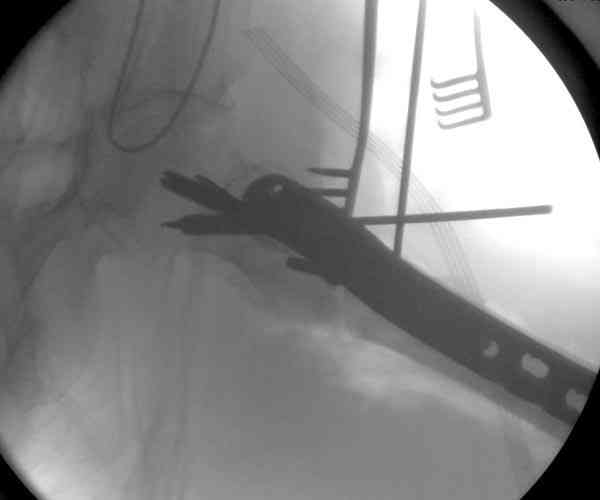

Из-за ослабленного латерального кортекса в проксимальной части бедра (прорезавшийся первичный неудачный штифт) штифт для фиксации не годится. Потом для установки современных блокирующих штифтов необходимы дополнительные оборудования и опыт применения.

Адекватная фиксация достигается длинным 95 градусным Blade Plate, где клинок пластины, связывая головку со средней трети бедра, создал бы условия для сращения.

Другой вариант пластины, это Synthes Proximal Locking Plate предназначенный для лечения прксимальных переломов бедра, где три шурупа: два 7.3 мм, введенных в головку под углом 95, 120 и 5.0 мм в 130 градусов, создают угловую стабильность.

Профилактику прорезывания шурупов в кости можно добиться введением в отверстие цемента, потом проведением шурупа, цемент, застывая, удерживает шуруп в правильном положении.